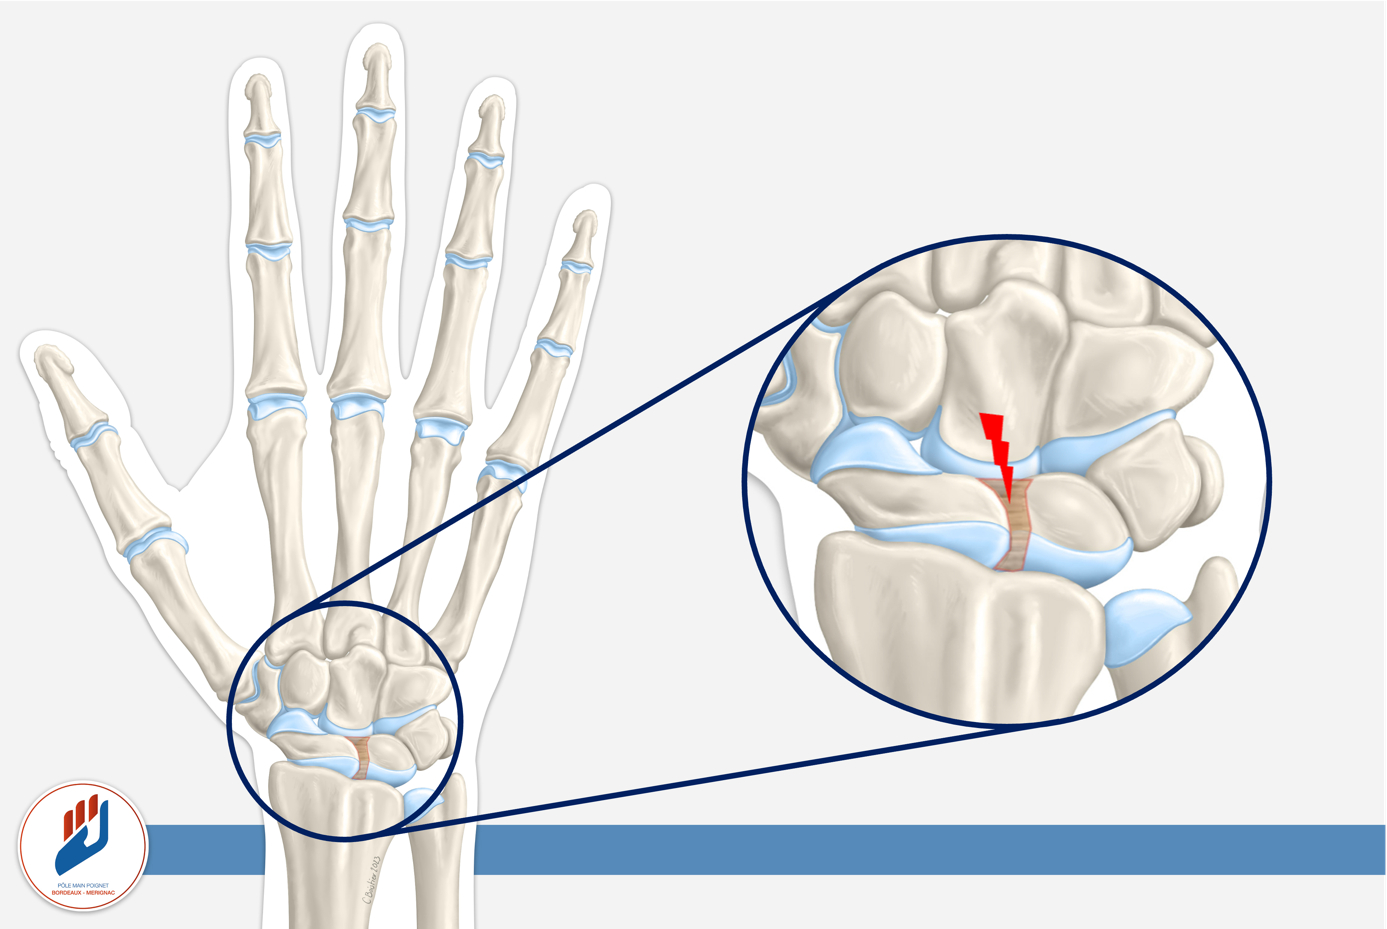

Le ligament scapholunaire (ou SLIL, scapholunate interosseous ligament) relie deux os centraux du carpe : le scaphoïde, situé du côté du pouce, et le lunatum, au centre du poignet.

Ce petit ligament joue un rôle majeur : il synchronise les mouvements de ces deux os, garantissant la stabilité du poignet lors des gestes de force, de torsion ou d’appui.

Lorsqu’il est rompu, le scaphoïde et le lunatum perdent leur coordination : ils bougent indépendamment l’un de l’autre, créant une instabilité scapholunaire.